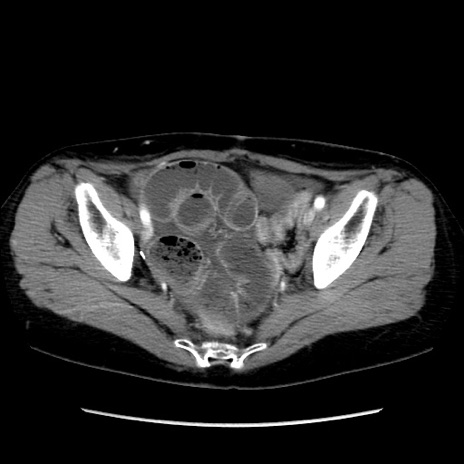

矢状断像

【症例】40歳代 女性

【主訴】上腹部痛、嘔気・嘔吐

【現病歴】約9時間前頃から急に上腹部痛、嘔気、嘔吐が出現。改善しないため救急要請。

【既往歴】子宮頚癌(広汎子宮全摘術、放射線療法)、腸閉塞

【身体所見】腹部:平坦、軟、腸雑音亢進、上腹部を中心に腹部全体に圧痛あり。

【データ】WBC 8400、CRP 0.03